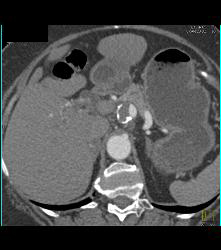

Celiac Artery Aneurysm